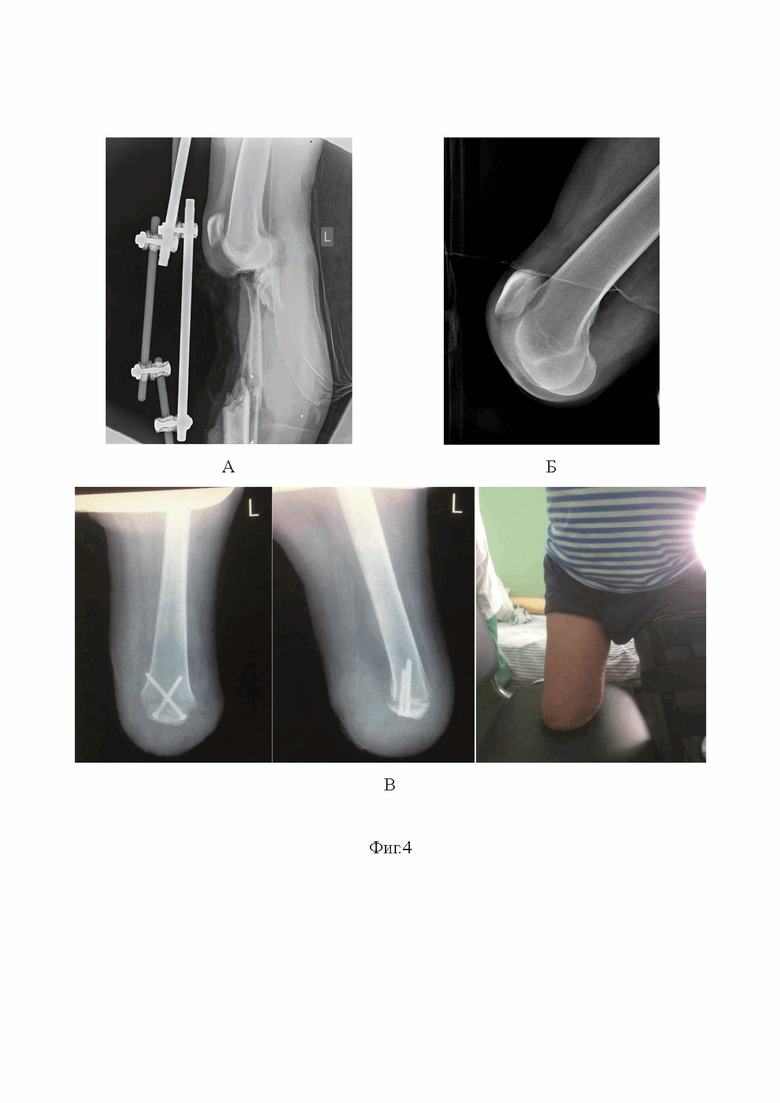

Изобретение поясняется фиг. 1, на которой показано формирование короткого заднегокожно-фасциального лоскута, на фиг. 2 представлено выполнение остеотомии параллельно чрезнадмыщелковой линии, на фиг. 3 приведена схема фиксации надколенника к опилу бедренной кости двумя винтами: А - схема ампутации (удаляемые участки кости заштрихованы), Б - оставшаяся после опила часть надколенника на переднем лоскуте переносится на опил бедра (указано стрелкой), В - сверлом просверливаются отверстия под винты под острым углом менее 90 градусов, Г - зенкером обрабатывается наружный кортикал надколенника под головки винтов, Д - выполнена фиксация надколенника двумя винтами. На фиг. 4 изображены: А - первичные рентгенограммы, Б - рентгенограммы после экзартикуляции, В - рентгенограммы после операции и внешний вид культи.

Пациент Г. 40 лет, в ходе исполнения служебных обязанностей в ходе СпВО получил минно-взрывное ранение левой голени с обширным дефектом мягких тканей и разрушением диафиза большеберцовой кости на протяжении 15 см. Первичные рентгенограммы представлены на фиг. 4А. При поступлении в клинику военной-травматологии и ортопедии на этап СМП 3 выполнена экзартикуляция на уровне коленного сустава (фиг. 4Б). После стабилизации состояния пациента, нормализации гемодинамических показателей, спустя 2 недели выполнена костно-пластическая надмыщелковая ампутация бедра с применением усовершенствованного способа фиксации надколенника двумя винтами (фиг. 4В). Через 2 недели после операции выполнено удаление послеоперационных швов, пациент осмотрен специалистом по протезированию, взяты мерки приемной гильзы для протеза. Через месяц после операции выполнено первичное протезирование, анатомический и функциональный результат позволил пациенту активизироваться и осуществить первичное протезирование в более ранние сроки, чем при классической операции Гритти-Шимановского, при которой протезирование возможно не ранее чем через 3 месяца после ампутации.